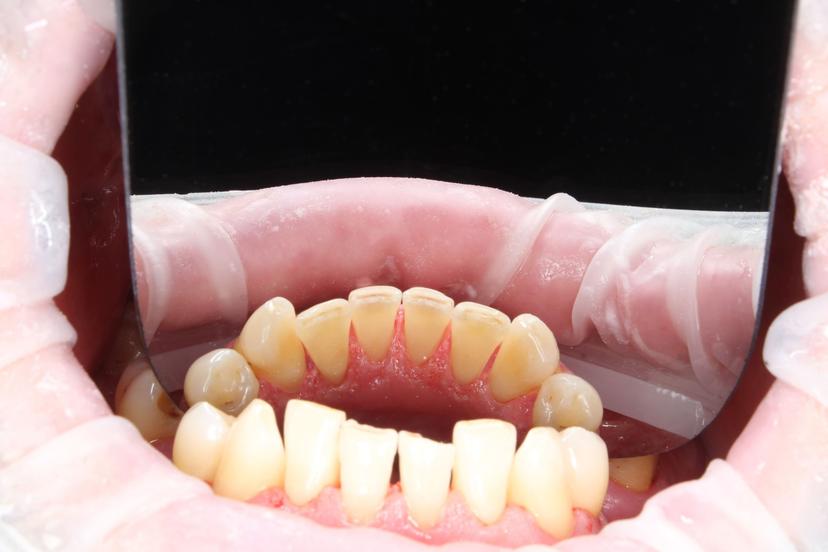

ДО: Заметны налет, пигментация и твердые зубные отложения, что придает неухоженный вид зубам.

После: Поверхность зубов очищена, восстановлен их естественный цвет, отсутствуют твердые зубные отложения и налет. Зубы выглядят здоровыми и ухоженными, а десны - свежими и более розовыми.